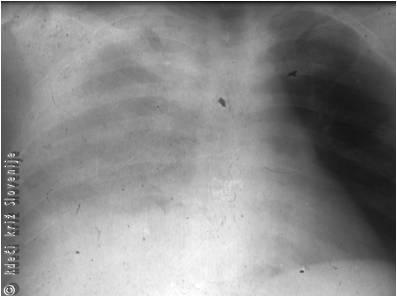

Slika 2 prikazuje poškodbo moškega, ki mu je pri prometni nesreči kos izolacijskega gradbenega materiala predrl prsni koš (Slika 2A). Reševalci so ukrepali pravilno, ker mu tujka niso poskušali odstraniti. Tujek je prsni koš predrl in poškodoval pljuča (Slika 2B). Takojšna operacija je rešila poškodovanca, ki je okreval brez zapletov.

Slika 2

A – Predrtje prsnega koša s kosom plastike.

B – Slika računalniške tomografije kaže velik tujek, globoko zadrt v levo stran prsnega koša.